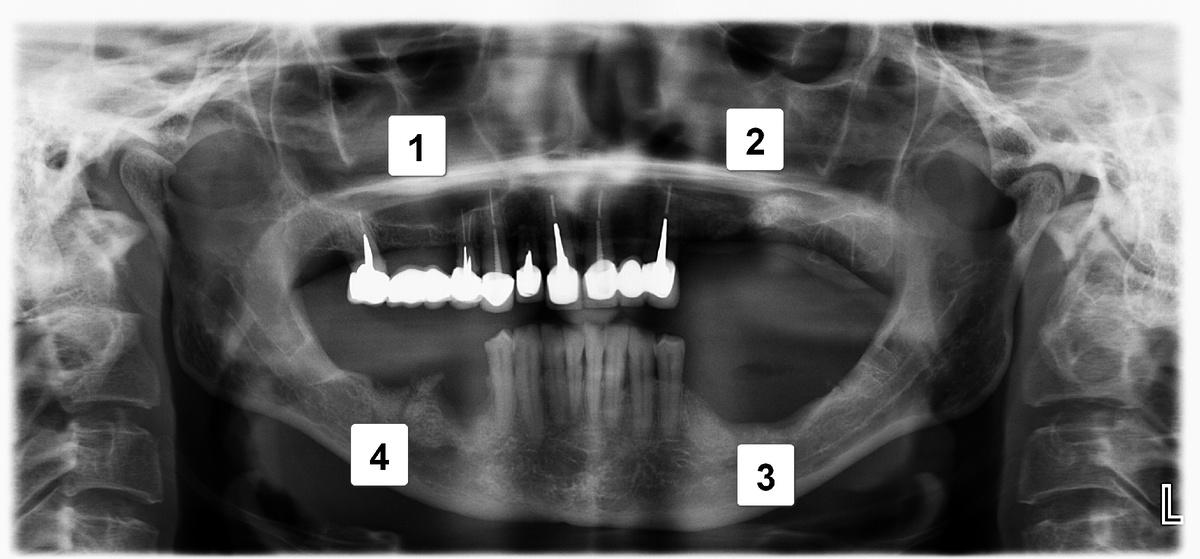

Диагностика и клиническая картина

На рентгеновском снимке ситуация в полости рта выглядит следующим образом:

Проблемы:

1 — атрофия костной ткани в области ранее удаленных 5 и 6 зубов на верхней челюсти справа.

2 — атрофия костной ткани до первого витка имплантов в области 4, 5 и 6 зубов на верхней челюсти слева

3 — внушительный «карман» между зубом мудрости и коронкой на импланте, проведение гигиены которого в домашних условиях было невозможно

4 — выраженная атрофия костной ткани, убыль десны, оголение имплантатов, воспаление, гноетечение

5 — экстремальная атрофия костной ткани в области импланта 5-ого зуба, воспаление мягких тканей, гноетечение

6 — симметричный «карман» слева, между зубом мудрости и коронкой на импланте

7 — клиновидные дефекты (абфракции) и закономерная рецессия (опущение) десны

Позитив:

Сохранившиеся зубы во фронтальном отделе, и снизу, и сверху, подарили нашей героине последний шанс восстановить зубы без искусственной розовой десны